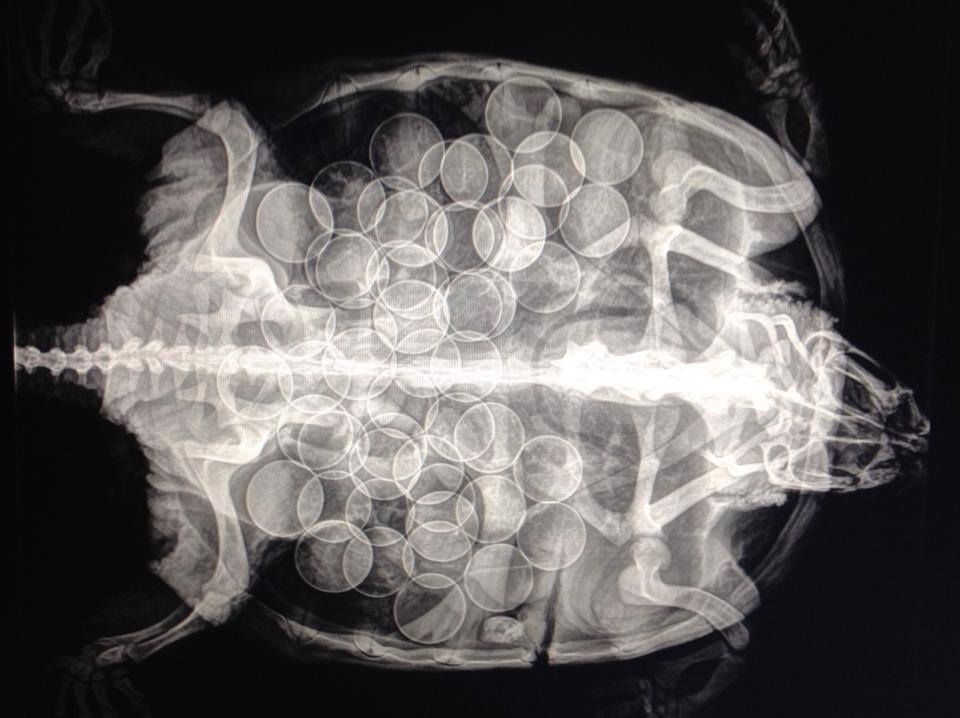

• Reptiles (except for venomous) – lizards, snakes, turtles, and tortoises

• Diagnostic imaging including radiographs, ultrasound, endoscopy, and CT